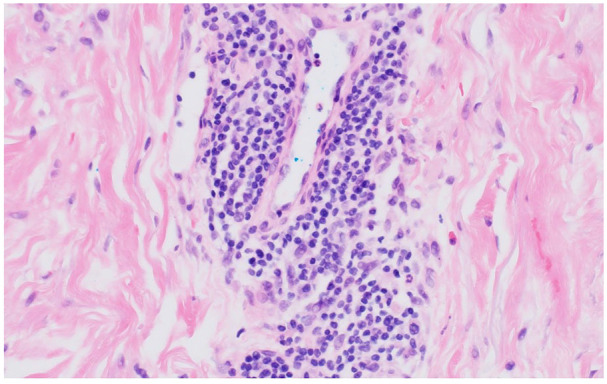

When there is concern that a rash may be a drug eruption reaction, there are many well-known culprits such as antibiotics and phenytoin. When an uncommon or previously unknown offending medication is being considered to have caused a drug eruption, diagnostic skin biopsy can help confirm the diagnosis. Our patient is a 54-year-old female with past medical history of prediabetes and obesity. She had ST segment-elevation myocardial infarction that was treated appropriately with timely percutaneous coronary intervention, which included angioplasty and drug-eluting stent placement. She was maintained on treatment regimen, and over the next 3 months, she developed a worsening maculopapular rash across her torso and upper extremities. Her biopsy showed superficial and mid-dermal perivascular lymphohistiocytic inflammation with focal spongiosis and scattered eosinophils, a common pathologic finding seen in drug eruptions. Although the patient was not taking any well-known offending agents, her ticagrelor was discontinued and she was transitioned to clopidogrel. Shortly after the transition, the patient's drug rash resolved without recurrence. Drug eruptions are a common etiology for rashes leading to presentation in primary care clinics. Our patient illustrates an exceedingly rare case of ticagrelor-induced drug reaction, as a review of the literature shows only 2 previously published case reports.